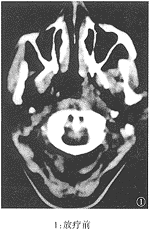

本组病例经随访观察3月~35月,平均17月(中位数15月)。除2例再粘连外,均取得了良好的通气效果。该组的CT显示:鼻腔粘连的部位多在鼻腔后份,表现为鼻甲与鼻中隔之间的空隙消失,为条索状致密阴影所填充,往往可在多个层面特别是在鼻腔的上部层面上可以观察到。治疗前后鼻甲与鼻中隔间的空隙恢复见图1、2、3。

附图 鼻腔粘连前后及手术治疗后的鼻腔CT表现

临床诊断鼻腔粘连不难,凡NPC放疗后有持续性鼻塞并伴流涕、嗅觉减退或丧失者,经鼻镜检查发现下、中鼻甲与鼻中隔相贴,用血管收缩剂不能分开,探针不能通过,粘连即可确诊。通过对经治疗的28例鼻腔粘连病例的鼻咽轴位CT的观察,发现鼻腔粘连的轴位CT有以下特点:鼻甲与鼻中隔之间的空隙消失,被条索状致密影代替;这条索状致密影往往可在多个层面特别是在鼻腔顶部的层面上观察到,而肿胀的鼻甲组织的密度较为均匀且以鼻腔下部为主,可以与因放疗引起的鼻腔粘膜肿胀及鼻腔分泌物相区别。与粘连前的CT片比较,也有助于CT上对该病的诊断。